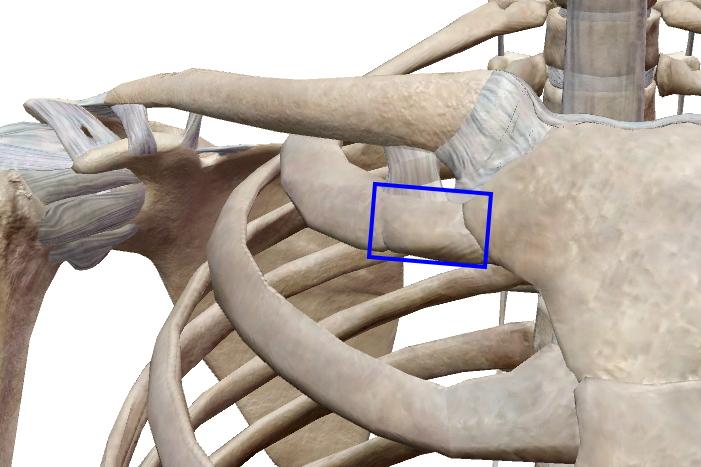

球関節

| 皿、もしくは臼状の関節窩を持つ骨と、球状の関節頭を持つ骨からなる関節。前後・左右と軸を保った回旋が可能な多軸関節。 股関節、肩関節、腕橈関節。*椀等関節は腕尺関節との兼ね合いがあるので2軸に近い |